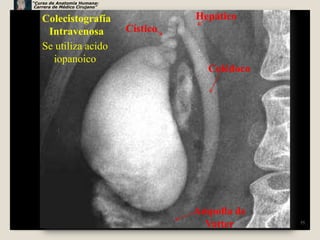

Colecistografía                      Hepático

Intravenosa               Cístico

Se utiliza acido

iopanoico

Colédoco

Ampolla de

Vatter      55